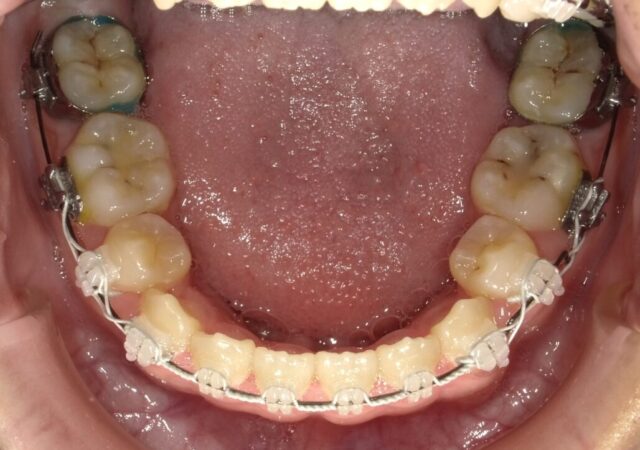

≪下顎咬合面観≫

2025年1月